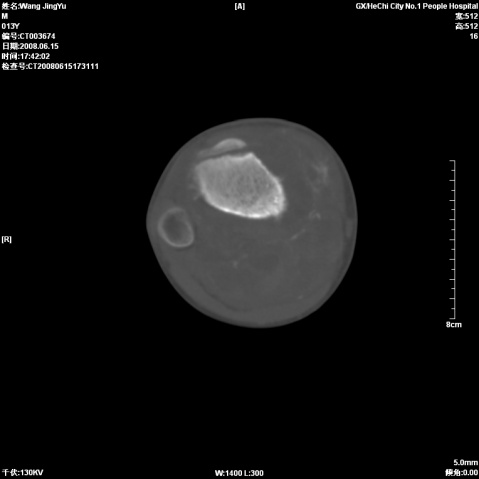

以下是引用随光逐影在2008-6-23 15:30:00的发言:[br]胫骨中上段骨肉瘤(临床表现:好发年龄+好发部位。ct表现:骨质破坏+肿瘤新生骨+骨膜反应并破坏,形成codman氏三角+软组织肿块)。